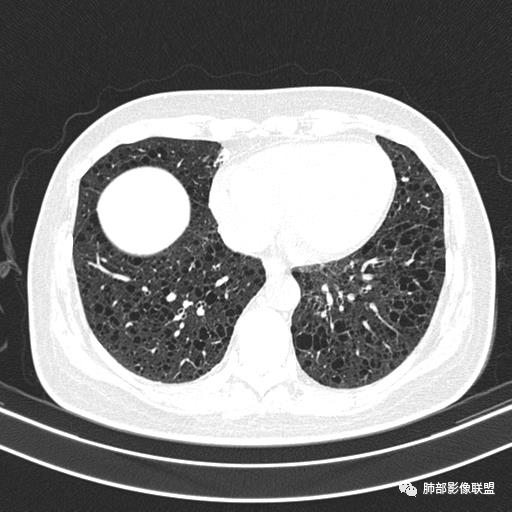

双肺弥漫囊腔,累及肋膈角,囊腔形态相对规则单一。

CT平扫示双肺弥漫分布大小不等囊状薄壁透光区,无内、中、外带分布差异,间质稍示增厚。拟LAM

女,46,活动性气喘1年。苯吸入史半年。胸部CT:两肺弥漫囊腔,上至肺尖,下至肋膈角,形态类似小囊腔。考虑:LAM,鉴别LIP,BHD,PLCH等。

双肺多发大小相近的囊状影,分布趋势趋于一致,中年女性,考虑LAM。部分囊内见血管及分隔影,小叶中心性肺气肿代排

CT表现:双肺弥漫大小不等的薄壁囊腔,囊壁<2mm,外形规则,血管影多位于囊腔周围,囊腔之间肺组织正常,随着疾病进展到晚期,囊腔变大、增多,不可胜数,囊腔可融合成较大的囊,与肺气肿相似,形成间质性肺纤维化。部分病例可出现结节影。